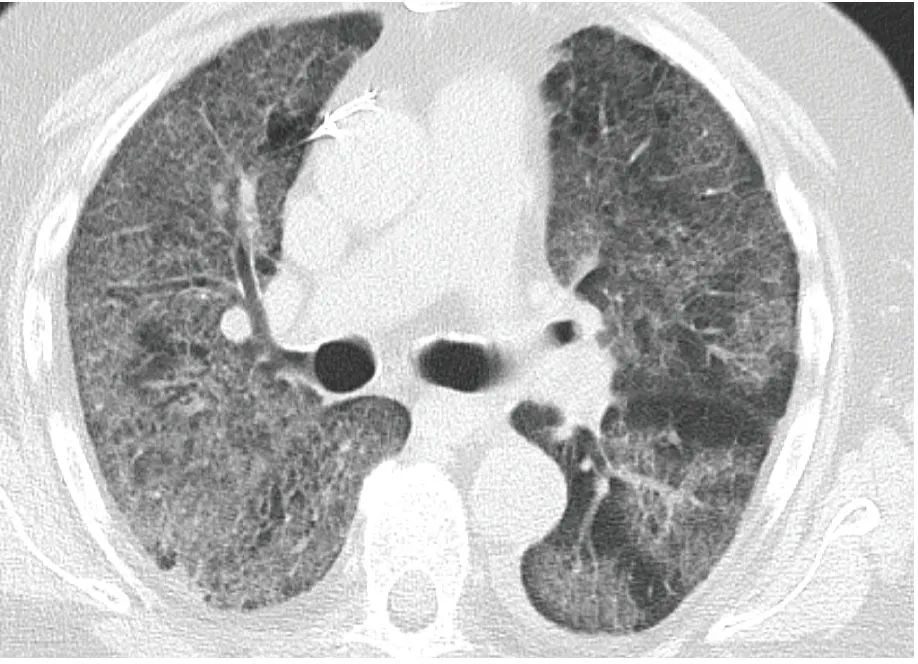

Noncontrast CT shows diffuse {{c1::ground glass}} opacification in which the pulmonary architecture, including {{c2::vasculature}} and {{c2::bronchi}}, can be still seen

--> which is characteristic for ground glass opacification

--> this was a case of acute respiratory distress syndrome (ARDS)